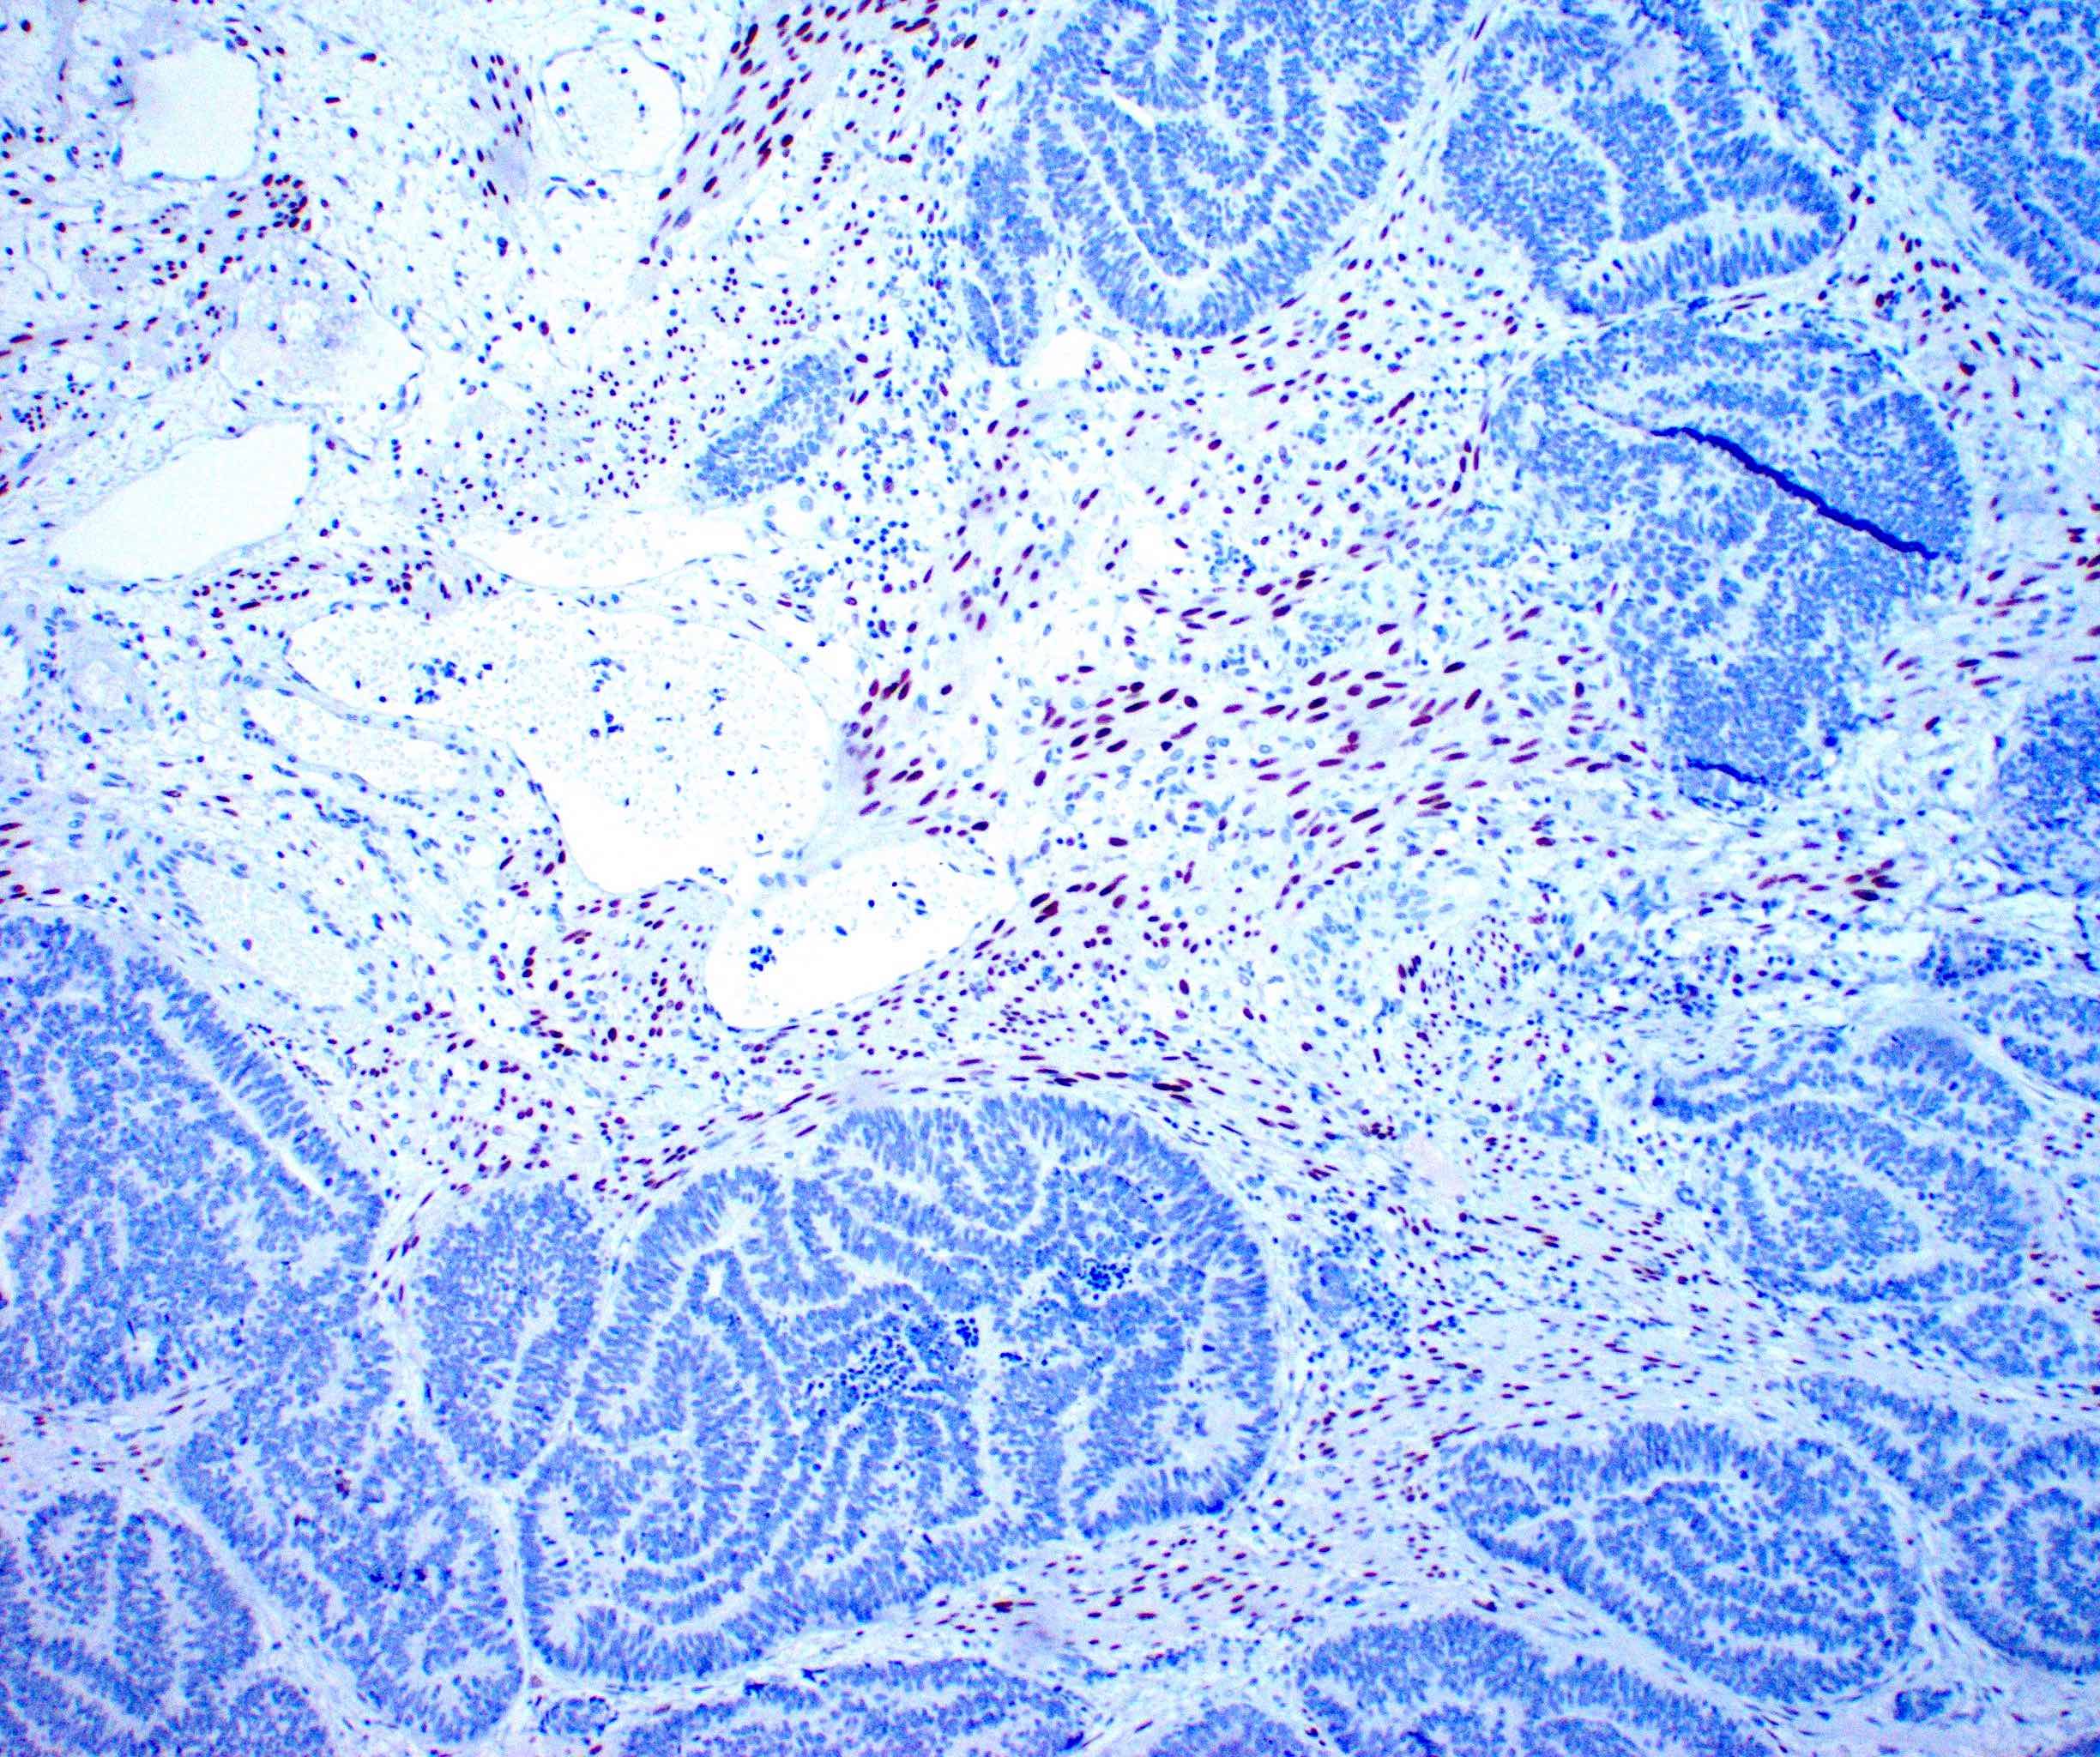

Microscopic (histologic) images

Contributed by Daniel Graham, M.D., Adele Wong, M.B., B.Ch., B.A.O. and Lucy Ma, M.D.

Microscopic (histologic) description

- Variety of histologic patterns that may be present within the same tumor

- Most frequently small tubules with ductal / glandular growth

- Papillary, solid growth, trabecular, retiform, sex cord-like, sieve-like, glomeruloid and spindle cell areas have all been described

- Luminal eosinophilic secretions are characteristic but not always identified

- Tumor cells can be flattened, cuboidal or columnar with mild to moderate cytological atypia

- Clear cell features can be seen but are less common

- High grade cytological atypia is usually not a predominant feature

- Nuclei show vesicular chromatin and nuclear grooves

- Sarcomatoid transformation has been seen in rare instances

- Squamous, ciliated or mucinous differentiation (metaplasia) are not present and there are no associated mesonephric remnants (J Clin Med 2021;10:698)